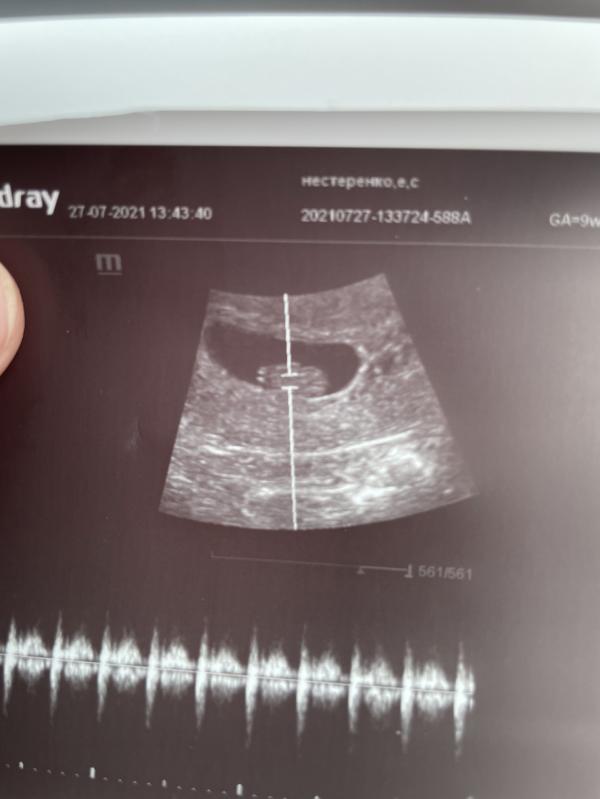

Была сегодня у гинеколога. Та сказала, что у меня «неадекватный прирост хгч», что на второй день задержки хгч должен быть 1000, а у меня всего было 61.. я также сдавала анализы вчера (15 дней задержки, если так считать) хгч был 8759. Гинеколог отправила меня на узи, чтоб исключить внематочную беременность, на узи выявили маточную, в 5 недель и чсс даже уже 115, ритмичное. НО узист поставила «продолговатая форма плодного яйца».